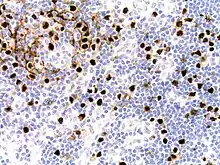

Micrograph of HHV8-associated Castleman's Disease showing LANA-1 positive lymphoblasts in a regressed germinal center and mantle zone. LANA-1 stain.

Formal criteria for the diagnosis of HHV-8-associated MCD have not been published; however, diagnosis requires enlargement of lymph nodes in multiple lymph node regions (typically confirmed with radiologic imaging), histologic changes consistent with HHV-8-associated MCD on biopsy of an enlarged lymph node, and confirmation of HHV-8 infection by LANA-1 lymph node staining or peripheral blood polymerase chain reaction for HHV-8.[6] HIV testing is useful for management, but a positive result is not necessary for to diagnose HHV-8-associated MCD.[2]

Staining with latency-associated nuclear antigen (LANA-1), a marker for HHV-8 infection, is typically positive.[11]